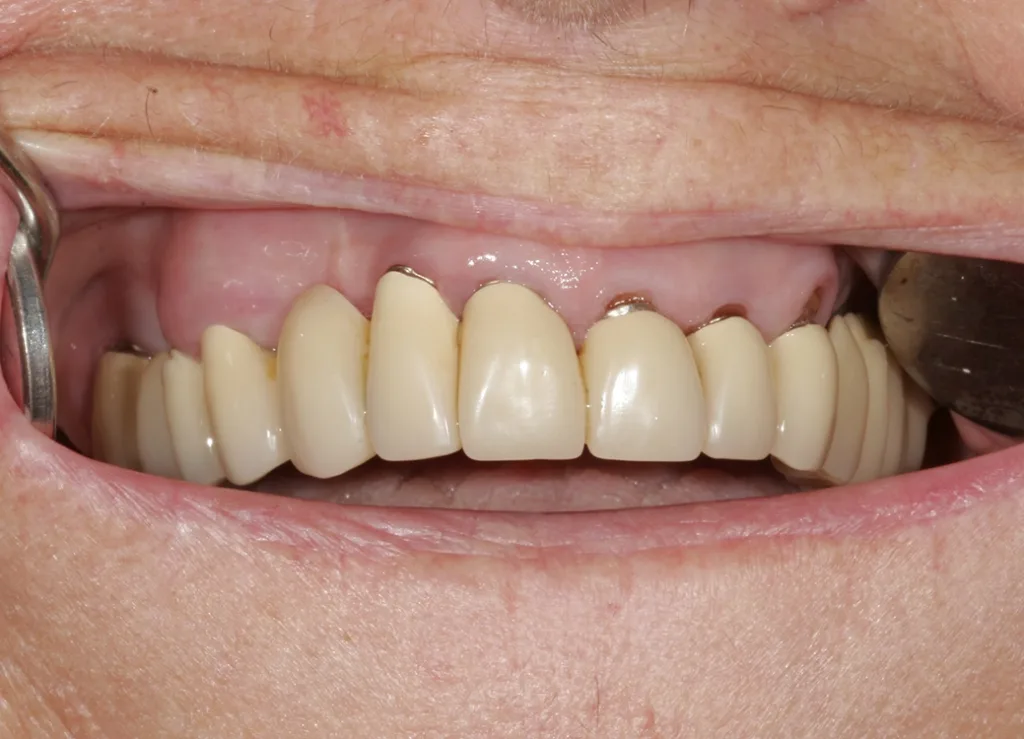

Beim ersten Patientenkontakt zeigte sich eine aufgrund der Situation sehr angespannte, unzufriedene Patientin; ein Lächeln war praktisch nicht möglich (Abb. 3). Obgleich die Oberkiefer-Teleskopversorgung (Abb. 4) im Zahnhalsbereich kosmetisch nicht mehr sehr schön war, fiel dies aufgrund der stark deckenden Oberlippe in situ nicht auf. Funktionell war die Versorgung nach wie vor ohne jegliche Beanstandung, was sehr für den damaligen Techniker ebenso wie auch für die Teleskoptechnik selbst spricht. Die alte VMK-Brücke im Unterkiefer (Abb. 5) war ästhetisch noch immer in einem guten Zustand. Bei genauerer Betrachtung wurde die grazile Ausführung ersichtlich; bei 31 und 32 mesial schimmerte der Opaker im Halsbereich leicht durch, was darauf schließen ließ, dass das Platzangebot hier nicht übermäßig groß war. Aufgrund der Grazilität der Zähne kann in diesem Bereich oft nicht viel nachpräpariert werden; entsprechend schwierig ist es, in solchen Fällen mit Doppelkronen ein ästhetisch befriedigendes Ergebnis zu realisieren.